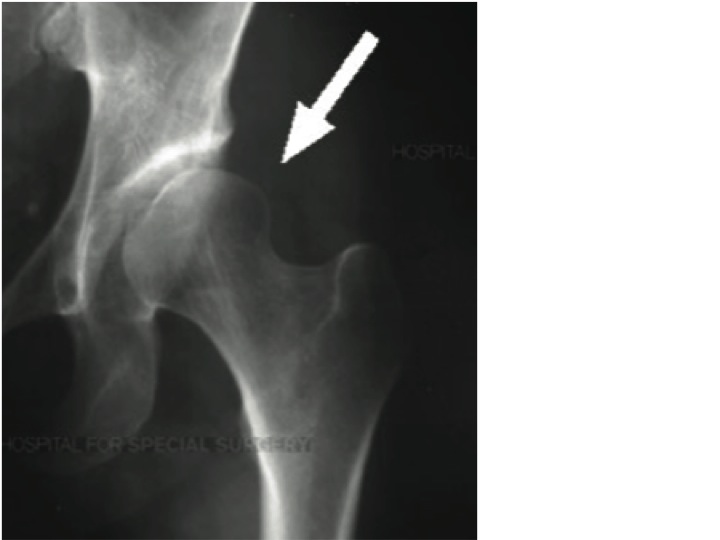

Femoral Acetabular Impingement (FAI) is defined as the mechanical abutment of the femoral head against the acetabulum1. This contact is either structural (cam or pincer lesion), functional or a combination of both and results in pain, loss of motion, and disability.

Researchers have questioned if the findings noted on x-ray are a normal morphological changes based on anatomy and biomechanics or a structural pathology(3).